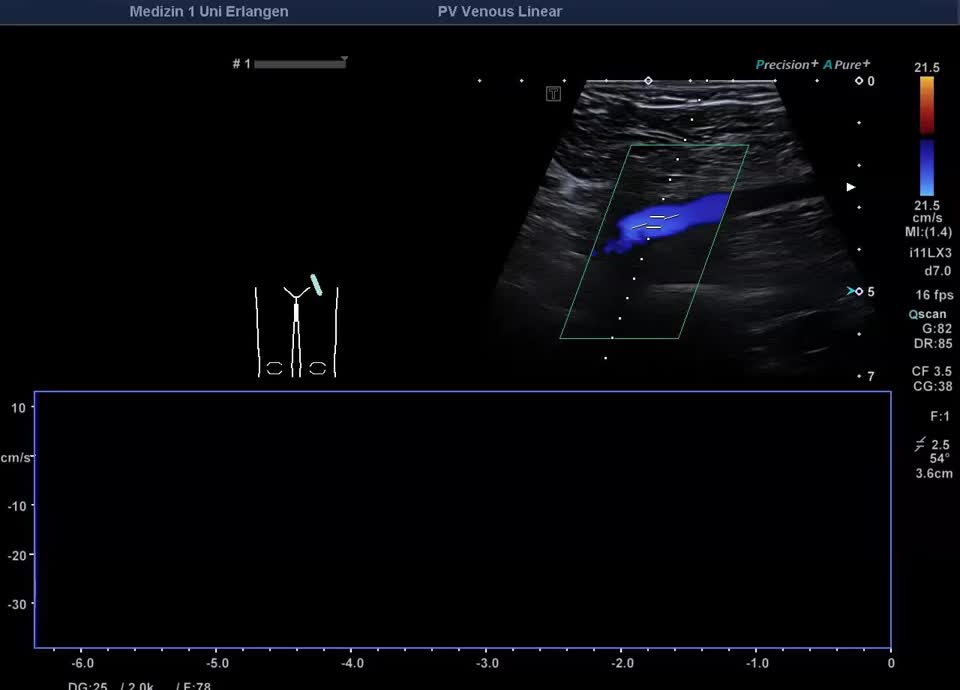

Normalbefunde

• Flussprofil V. iliaca externa Valsalva-Manöver (PW-Doppler)

• Regelrechtes Flussprofil V. iliaca externa (Farbdopplervideo)